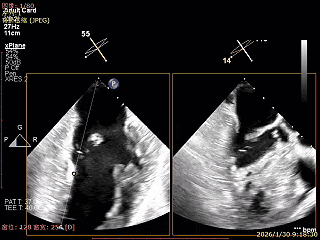

术前超声评估

经胸超声报告提示:患者二尖瓣2区及3区前叶关闭时脱入左房,二尖瓣重度反流(MR 4+),患者LA前后径约52mm,LVEDD约68mm,LVESD约42mm,EF值:65%,经胸超声测二尖瓣瓣口面积约6.1cm2,主动脉瓣无冠瓣脱垂并中重度反流,三尖瓣中度反流,估测中度肺动脉高压。

经食道超声精细化测量:肺静脉逆流,房间隔可穿刺高度约4.2cm,Flail宽度约21mm,Flail高度约8mm,Flail Gap约4mm, 3区AML长约23mm、PML长约12mm、2区AML约32.2mm,PML约16mm。

房间隔可穿刺高度约4.2cm

Flail宽度约21mm,Flail高度约8mm

经胸短轴测得瓣口面积约6.1cm2

3区前叶长度约22mm,后叶长度约11.6mm

2区前叶长度约32.2mm,后叶长度约16mm

2区Flail Gap约4mm